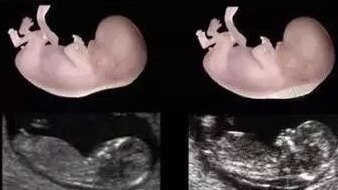

胎兒超聲檢查按照診斷級(jí)別,分為Ⅰ級(jí),Ⅱ級(jí),Ⅲ級(jí),級(jí)別越高觀察的內(nèi)容越多,對(duì)胎兒各個(gè)解剖結(jié)構(gòu)的觀察要求越高。孕20-24周的大排畸超聲是胎兒最重要的一次超聲檢查,所以醫(yī)院安排的是Ⅲ級(jí)超聲。二維,三維,四維是超聲觀察的手段。一般醫(yī)院超聲機(jī)器都有這些功能。因檢查需要而選擇不同的觀察手段。而二維是平面即為斷層解剖水平去觀察,三維即為3D立體觀察,有必要的時(shí)候超聲醫(yī)生會(huì)選擇三維成像來(lái)觀察,比如二維情況下提示唇腭裂,多指等。四維是在三維的基礎(chǔ)上加了一個(gè)時(shí)間緯度,即像動(dòng)態(tài)視頻。超聲檢查的目標(biāo)是臨床診斷,二維解剖學(xué)掃描和診斷是最主要的手段,三維四維是輔助檢查手段,有必要才應(yīng)用。打個(gè)簡(jiǎn)單比喻,Ⅲ級(jí)超聲是醫(yī)學(xué)專業(yè)證件照和三維四維是藝術(shù)照。專業(yè)照不可少,藝術(shù)照根據(jù)媽媽們心情可以選擇拍一拍留做紀(jì)念。 上面兩張三維圖,下面兩張二維圖 二維超聲掃描圖 左圖為超聲三維成像圖